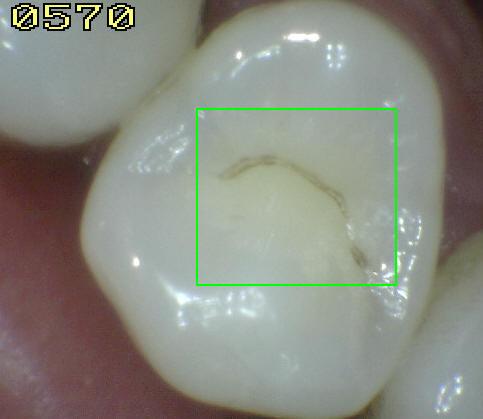

Código 2:

Lesión de caries observada en esmalte en estado húmedo y

permanece después de secar

- Al observar el

diente en estado húmedo verá una decoloración (mancha blanca

/ marrón)

en el fondo de la fosa y fisura y que desborda hacia las

paredes. (mas ancha que la fosa y fisura) las manchas

no tienen brillo y es consistente con desmineralización.